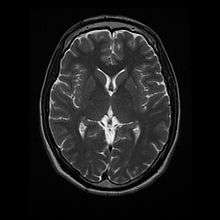

- T2: CSF is light, but fat (and thus white matter) is darker than with T1. T2 is useful for visualizing pathology.[14]

T1 (note CSF is dark) Normal axial T2-weighted MR image of the brain.

Normal axial T2-weighted MR image of the brain.